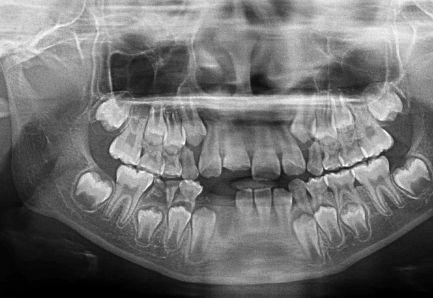

相关图片